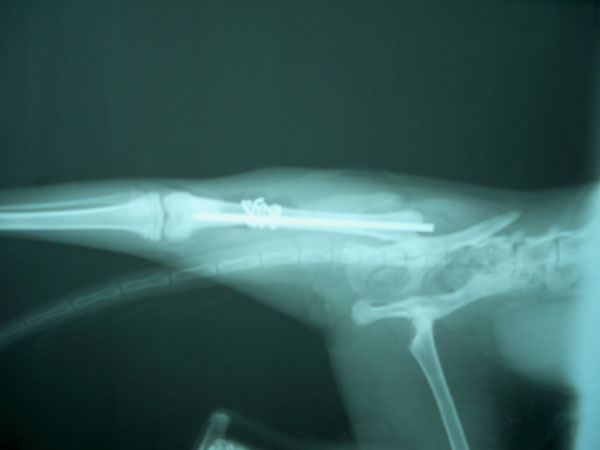

Για την αποκατάσταση του κατάγματος μετά την ανάταξη τοποθετήθηκε ενδομυελικός ήλος, ένας ήλος Kirschner εγκάρσια στην

καταγματική γραμμή με φορά απο την πρόσθια επιφάνεια προς την οπίσθια και κατα μήκος τοποθέτηση 4 μεταλλικών ραμμάτων κυκλοτερώς.